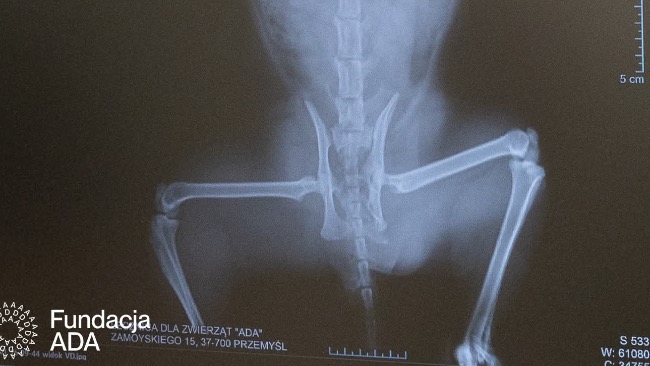

W klinice od razu rozpoczęliśmy walkę o jego życie. Po wstępnej stabilizacji wykonaliśmy badanie RTG – obraz był dramatyczny. Złamana miednica, poważne stłuczenia narządów wewnętrznych, ogromny ból przy każdym dotyku.